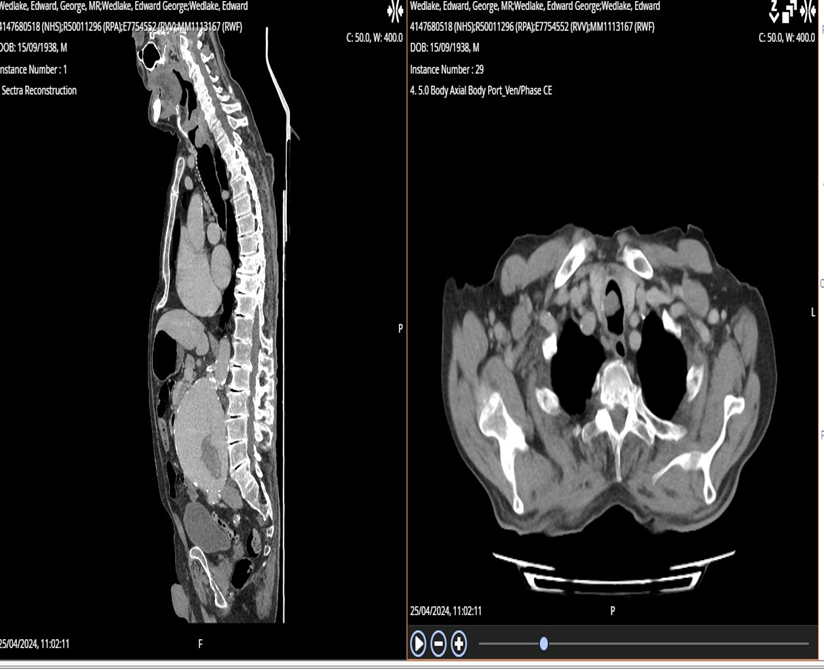

Progressively, he developed inspiratory stridor. A computed tomography (CT) scan of the neck, thorax, and abdomen revealed a 20mm mass in the proximal trachea, just below the epiglottis, with narrowing of the airway at the level of the vocal cords, likely secondary to oedema. In addition, there were enlarged bilateral

parotid and submandibular glands as described. The airway appeared patent radiologically. There was also an area of tree-in-bud nodularity in the right lung, likely infectious or inflammatory, which should be followed up on subsequent imaging.

Figure 1: CT scan showed 20mm mass in the proximal trachea just below the level of the epiglottis. There was also narrowing of the airway at the level of the vocal cords which looks to be secondary to oedema.